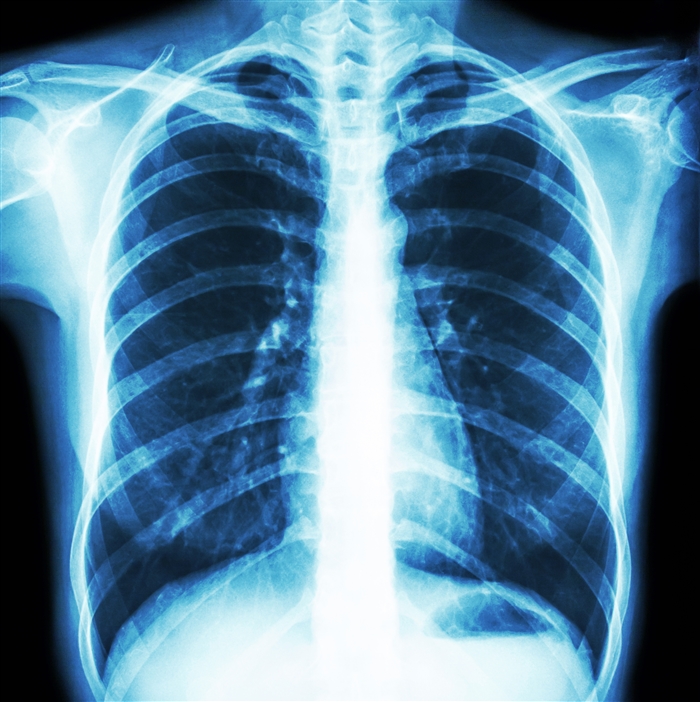

胸部レントゲン

健診でおなじみの簡単な検査ですが、

肺だけではなく

心臓の異常や大動脈の異常など、

様々な病気の診断に役立ちます。

| 胸部レントゲン | 肺を調べるレントゲンですが、心臓の大きさなどもわかり、心臓の異常の発見につながります。 |